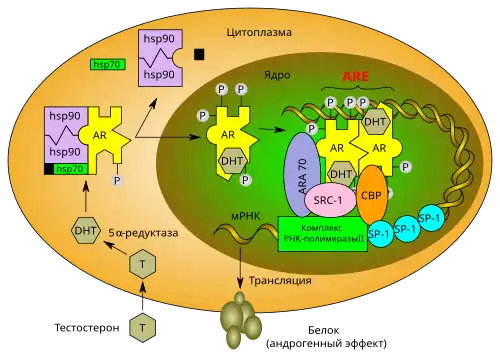

Сигнальный путь андрогенового рецептора включает в себя следующие этапы. После проникновения тестостерона в клетку-мишень он связывается с андрогеновым рецептором или непосредственно, или после превращения в более метаболически активную форму — 5α-дигидростерон (DHT) — под действием фермента 5-альфа-редуктазы[28]. DHT образует более стабильный комплекс с AR, и действие комплекса AR-DHT в 3—10 раз более сильное, чем комплекса AR-тестостерон. Связывание лиганда с рецептором в цитоплазме вызывает диссоциацию комплексов шаперонов (в том числе белков теплового шока, а именно Hsp70, Hsp90 и p23), которые в состоянии покоя находятся в связанном с AR состоянии и защищают его от деградации. Одновременно в рецепторе происходят конформационные изменения и фосфорилирование, в результате которых он транслоцируется в ядро. В ходе этих преобразований образуется сайт связывания с коактиваторами (AF-2-сайт)[3][29], а домен LBD перестраивается из трёхслойной, напоминающей сэндвич структуры из α-спиралей в более компактную структуру путём перемещения С-концевой спирали (спираль 12) в коровую часть белка[13].

В ядре комплекс рецептора с лигандом связывается с последовательностями-мишенями ДНК (элементами отклика на андрогены, ARE), которые располагаются в промоторах генов-мишеней. Структура ARE различается у различных генов, благодаря чему AR может выполнять множество регуляторных функций в пределах одного ядра. Усилению и большей специфичности взаимодействия AR с ДНК способствует наличие нескольких ARE (в самом деле, единичный ARE обычно обеспечивает лишь малую активность). Более того, специфичности ответа промотора на связывание с AR и усилению взаимодействия способствует наличие двух основных классов ARE. Последовательности ARE первого класса имеют вид RGAACA-NGN-TGTNCT (AR связывается с подчёркнутыми остатками гуанина); второго — RGGACA-NNA-AGCCAA (это связывание обеспечивает кооперацию двух соседних связанных с ДНК рецепторов и усиливает специфичность)[10]. Кроме того, ARE, как правило, являются сложными элементами и рядом с последовательностями связывания с AR содержат последовательности для взаимодействия с другими транскрипционными факторами[30], в числе которых транскрипционные факторы «домашнего хозяйства» (Sp1, CCAAT и NF-1), индуцибельные (NF-kB, Ets и AP-1) и тканеспецифичные транскрипционные факторы. Таким образом, AR регулирует экспрессию генов ещё и за счёт взаимодействия с различными транскрипционными факторами[13].

При связывании с ДНК андрогеновый рецептор димеризуется со второй молекулой AR, образуя антипараллельный димер[31]. В то время как для некоторых рецепторов стероидных гормонов показано образование гомодимеров в растворе и кристаллическом виде, AR не может образовывать димер in vitro[10]. Образовавшийся гомодимер рекрутирует дополнительные белки (РНК-полимеразу II, другие компоненты транскрипционного аппарата — TBP, TAF, другие общие факторы транскрипции (GTF) и другие ДНК-связывающие белки, например, сывороточный фактор отклика[32]) путём специфичного взаимодействия структурных мотивов. Это в конечном счёте приводит к активации или супрессии генов-мишеней андрогенов[3][29].